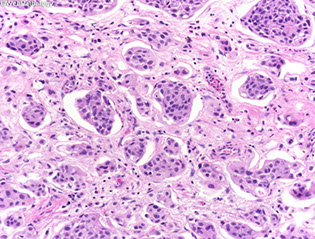

Nested urothelial carcinoma [2]

Nested urothelial carcinoma

- variant of urothelial ca originally recognized by its ability to mimic b9 conditions like proliferating von Brunn nests, esp in small bx's

- however, has a propensity to invade deep into bladder wall despite its low-grade morphology

- may be assoc c carcinoma in situ or conventional urothelial ca

- IHC: similar to typical UC (+ CK7 and p63, often CK20+)